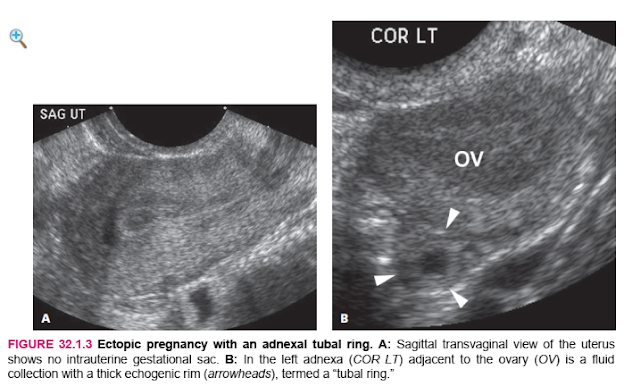

The sonographic finding that is definitive for ectopic pregnancy is visualization of a fluid-filled sac that lies outside the uterine cavity and contains either an embryo with cardiac activity (Figure 32.1.1) or a yolk sac (Figure 32.1.2). A more common, although less definitive, ultrasound finding in a woman with ectopic pregnancy is a complex extraovarian adnexal mass. In some cases, the mass is a fluid collection surrounded by a thick echogenic outer rim, termed a “tubal ring” (Figure 32.1.3), whereas in other cases, the mass has a solid or mixed solid and cystic appearance (Figure 32.1.4). There is sometimes a large amount of free intraperitoneal fluid and/or clotted blood in the pelvis (Figure 32.1.5).

HÌNH 32.1.2 Thai ngoài tử cung chứa một túi noãn hoàng. A: Hình ảnh trên siêu âm ngả âm đạo mặt cắt Sagittal của tử cung cho thấy không có túi thai trong tử cung. B: Hình ảnh mặt cắt Sagittal của phần phụ bên trái (SAG L ADN) cho thấy một túi thai (đầu mũi tên), chứa một túi noãn hoàng (mũi tên), nằm cạnh buồng trứng (OV)

HÌNH 32.1.3 Chửa ngoài tử cung với một vành ống dẫn trứng. A: Hình ảnh tử cung trên siêu âm ngả âm đạo cho thấy không có túi thai trong tử cung. B: Ở phần phụ bên trái (COR LT) tiếp giáp với buồng trứng (OV) là một chất lỏng bộ sưu tập có vành hồi âm dày (đầu mũi tên), được gọi là “vành ống dẫn trứng”.